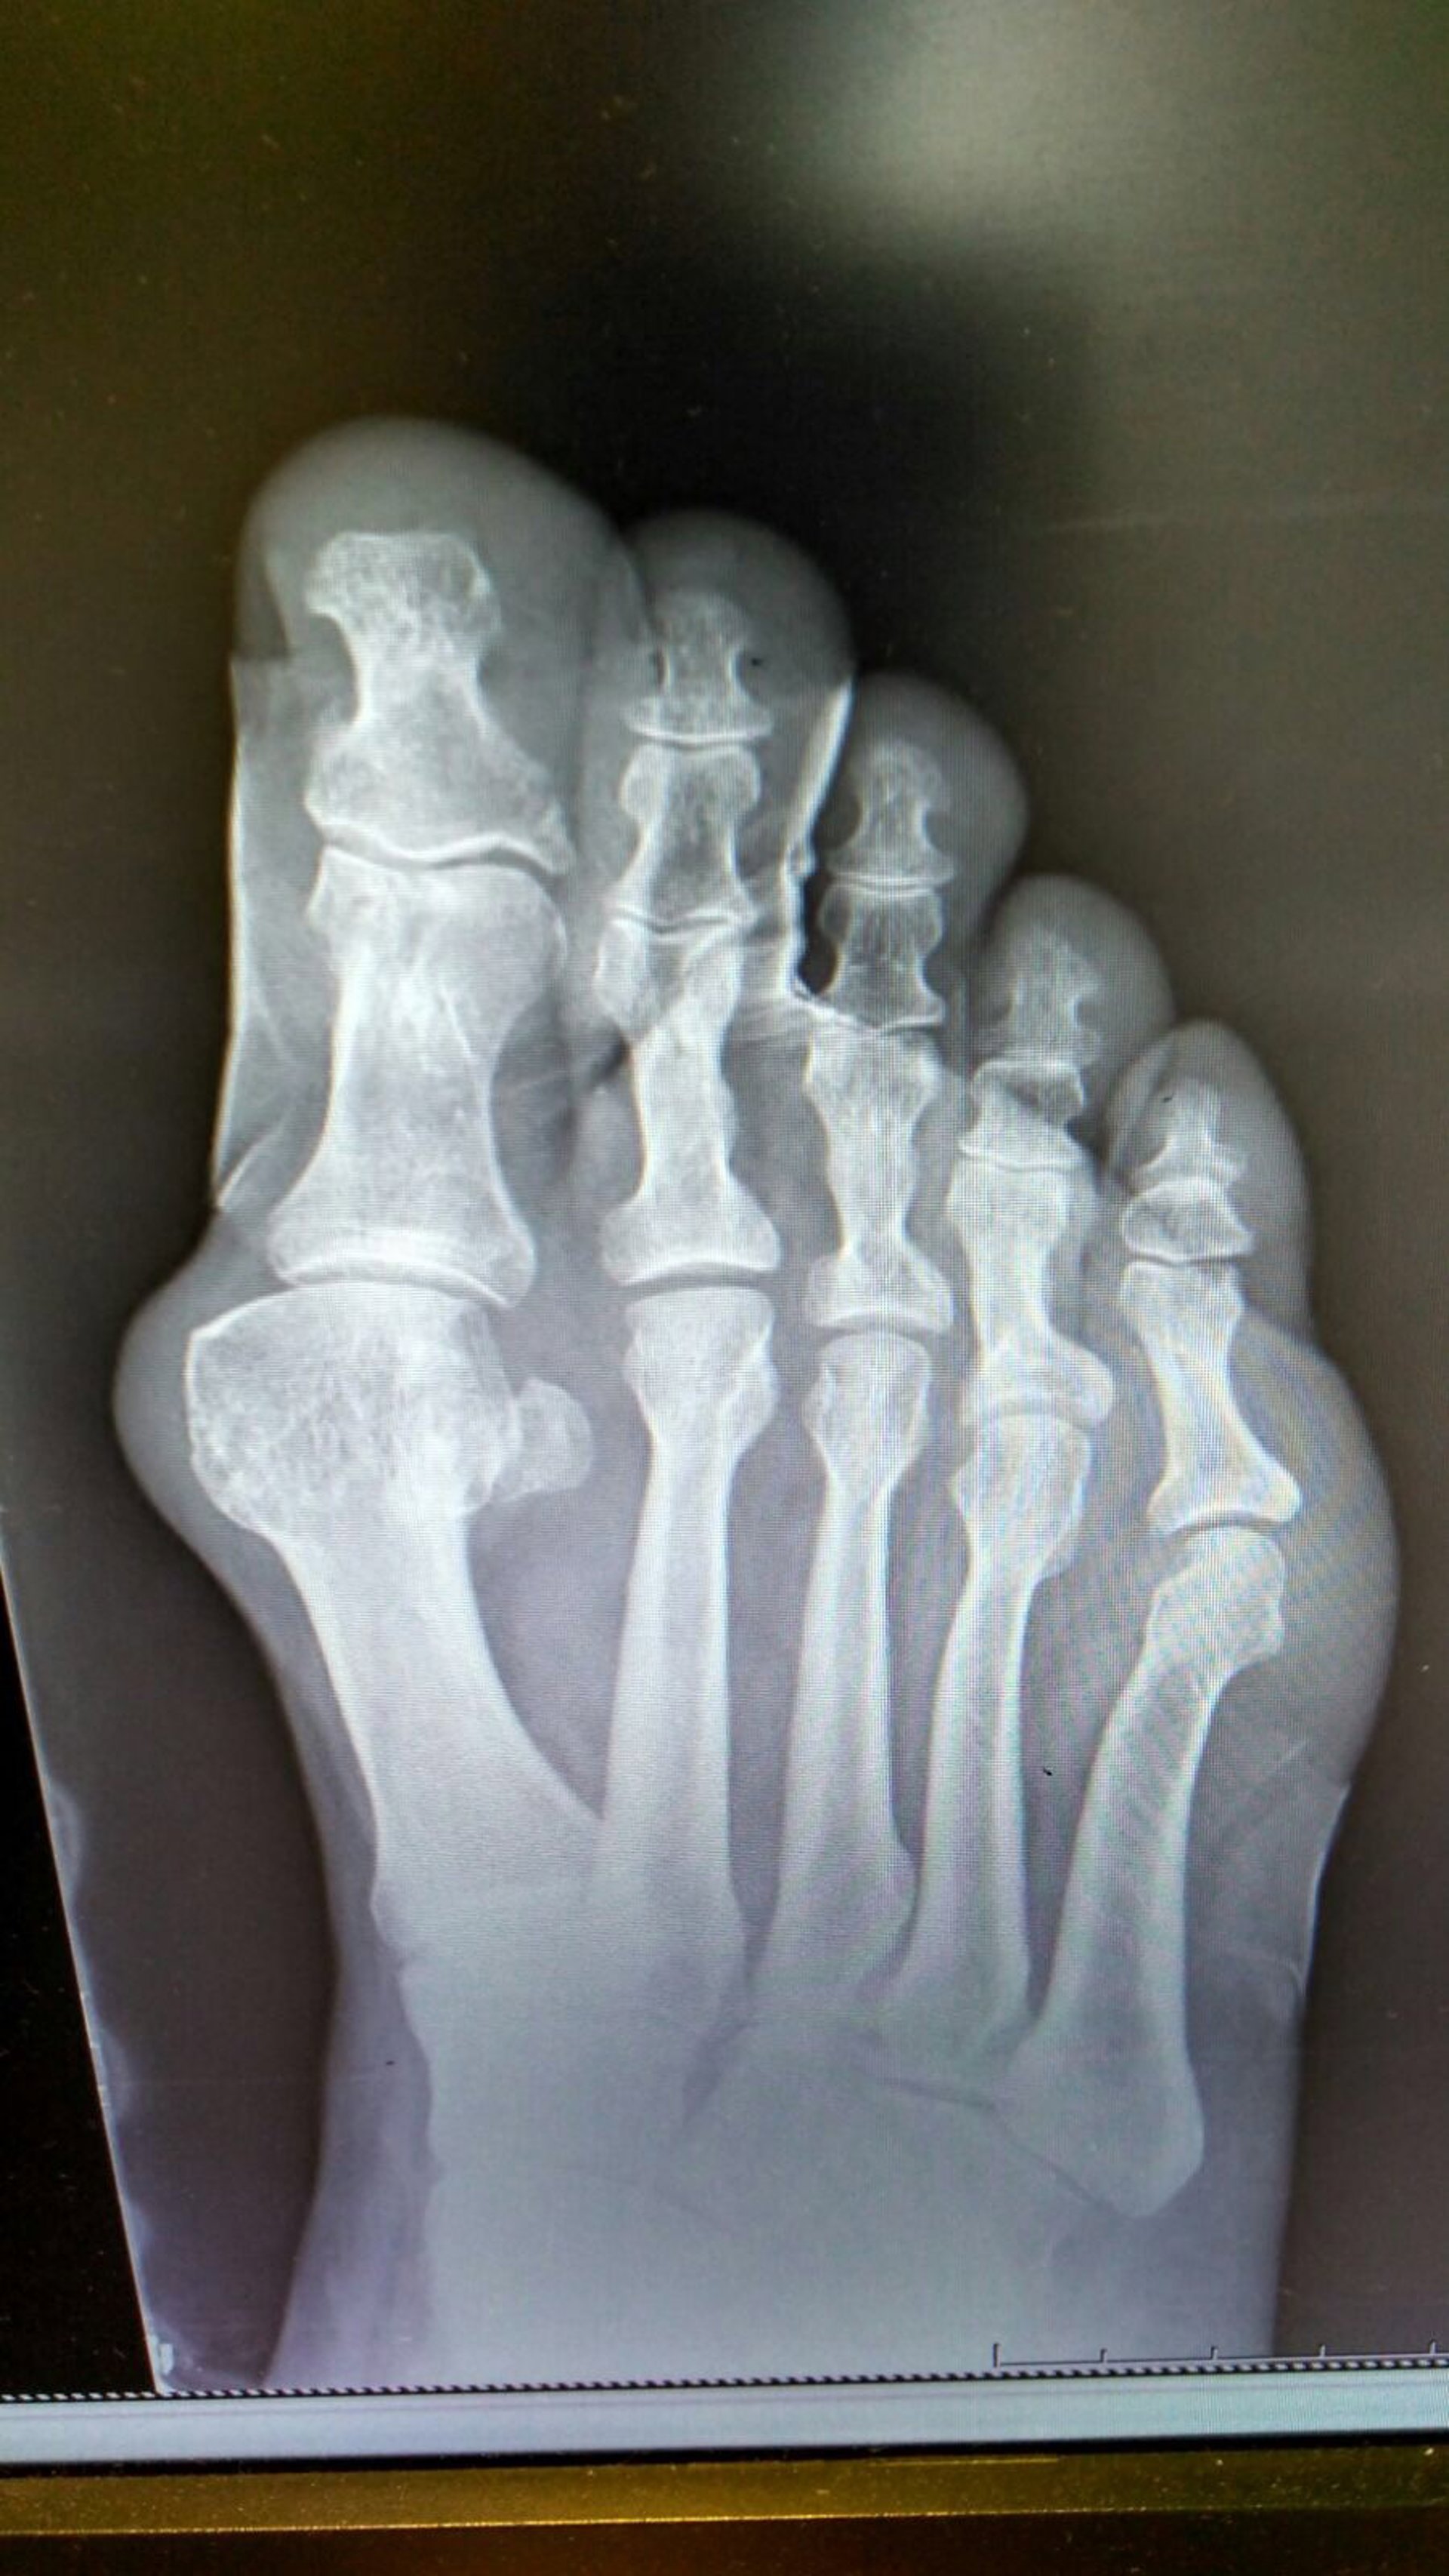

Archivo - Juanete

Archivo - Juanete - HOSPITAL LA LUZ - Archivo